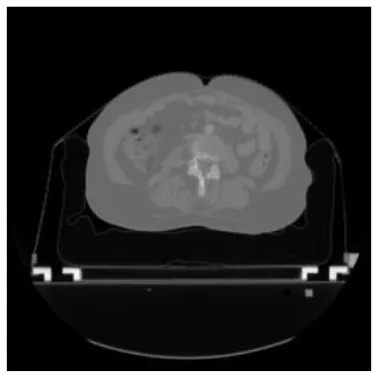

According to the acquired model parameters mentioned above, the testing set was calculated and examined. The performance of the modified algorithm for automatic organ segmentation in CT images is shown in Table 1. The organ contours segmented automatically by the algorithm were similar to those delineated by physicians manually. The model parameters including DSC, Accuracy, Recall, and Precision evaluation ones were served to evaluate the segmentation effectiveness of each organ in the validation and testing sets. In our work, the BCDU-Net CNN algorithm model was used to automatically segment different organs with the different training parameters such as epoch learning rate. The CT images which were randomly selected from the patients were put into the network model for training, and then the contours of different organs which were delineated automatically by the AI technology and manually by medical doctors were evaluated with the similarity coefficients, respectively. The results are given in Table 2. Most of the DSC values were better than 0.85 and among them the best even reached up to 0.9676. Generally, the automatic segmentation results met the requirements of clinical practice.

| Input CT image | Organs with manual segmentation | Organ with automatic segmentation | |

| Bladder | ![]() | ![]() | ![]() |

| Brainstem | ![]() | ![]() | ![]() |

| Eye-L | ![]() | ![]() | ![]() |

| Eye-R | ![]() | ![]() | ![]() |

| Femur-L | ![]() | ![]() | ![]() |

| Femur-R | ![]() | ![]() | ![]() |

| Heart | ![]() | ![]() | ![]() |

| Intestine | ![]() | ![]() | ![]() |

| Kidney-L | ![]() | ![]() | ![]() |

| Kidney-R | ![]() | ![]() | ![]() |

| Liver | ![]() | ![]() | ![]() |

| Lung-L | ![]() | ![]() | ![]() |

| Lung-R | ![]() | ![]() | ![]() |

| Mandible | ![]() | ![]() | ![]() |

| Rectum | ![]() | ![]() | ![]() |

| Spleen | ![]() | ![]() | ![]() |

| Stomach | ![]() | ![]() | ![]() |

The result of manual and automatic organ segmentation.